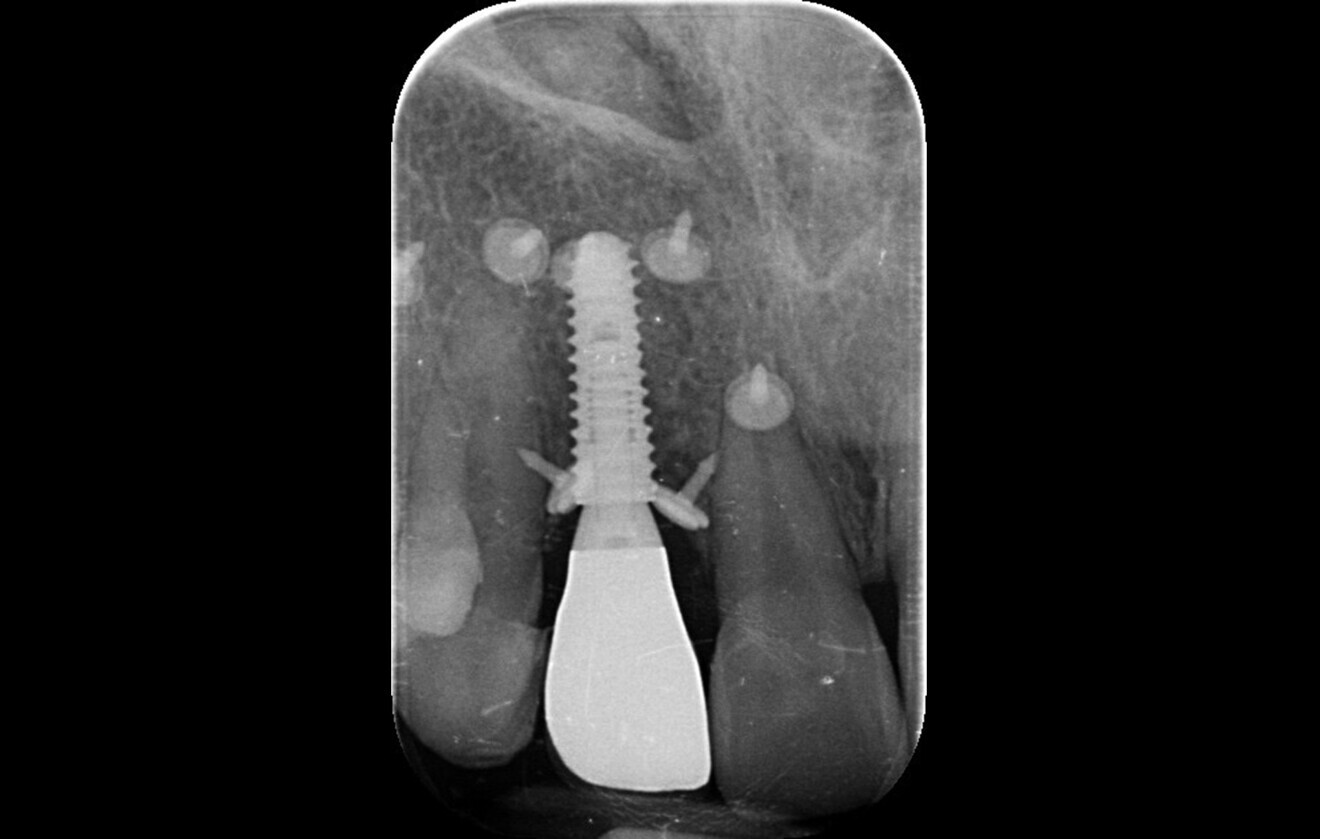

Fig. 2: CBCT evidence of labial implant malposition and bone loss.

Periapical radiographs showed bone contact on the mesial and distal aspects of the implant. However, clinical probing and CBCT revealed labial and palatal bone loss, consistent with a labially malpositioned implant (Fig. 2).